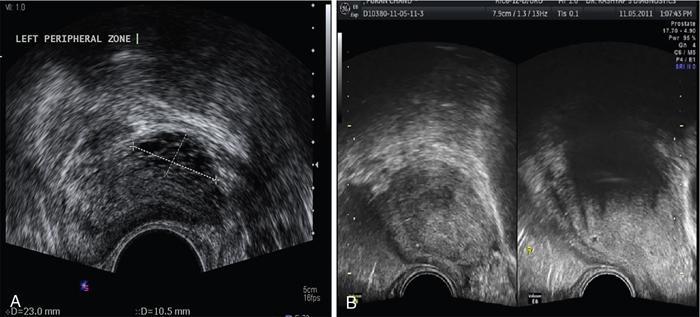

Prostate cancer

TRUS for staging of prostate cancer